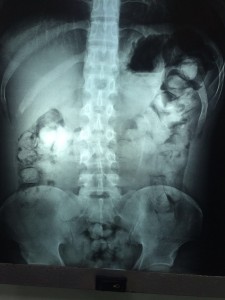

Segundo o tenente da Polícia Militar, Orlando Santos, Jefferson foi preso durante vistoria de rotina realizada no porto de Tabatinga, na manhã de sábado (19). Das 87 cápsulas, 25 delas estavam escondidas no bolso da calça do rapaz e amarradas ao calcanhar. As outras 62 estavam dentro do estômago dele.

O rapaz foi levado ao hospital do município para retirada da droga do estômago. Jefferson, que já responde na justiça do Pará pelo crime de tráfico de drogas, foi conduzido à sede da Polícia Federal em Tabatinga depois que recebeu alta médica para os procedimentos legais.